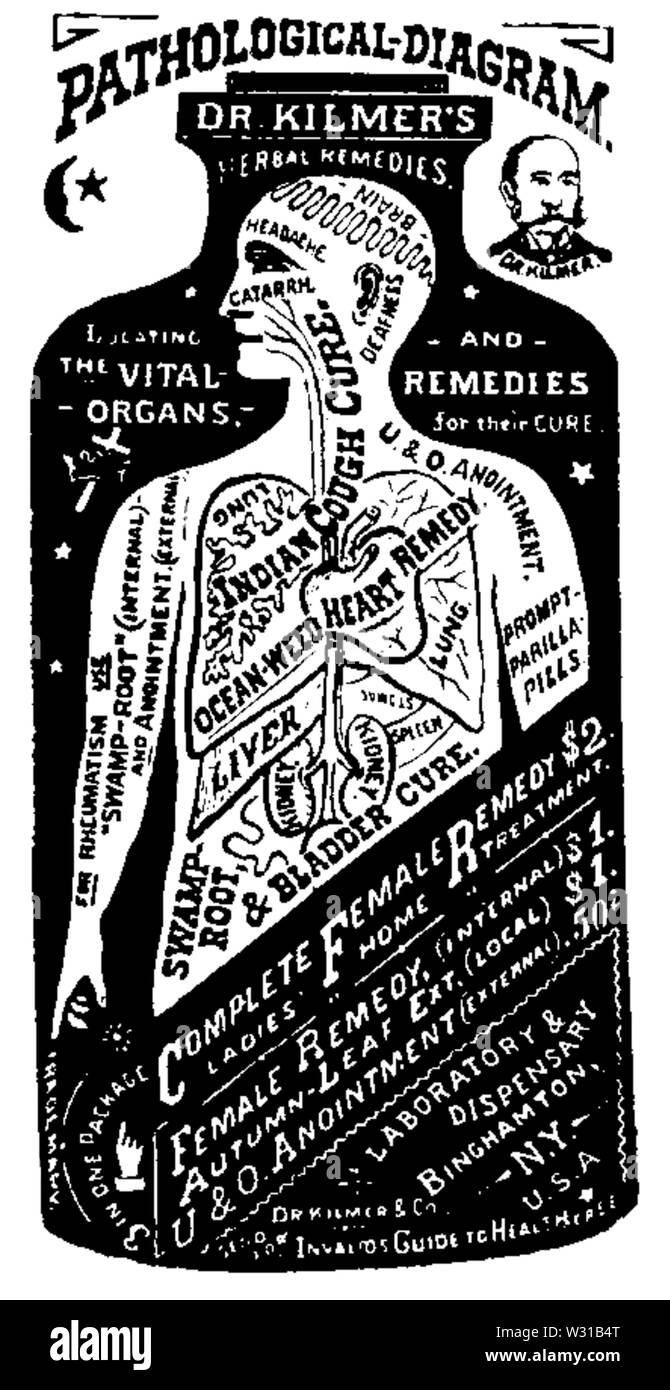

Schéma pathologique Banque D'Imageshttps://www.alamyimages.fr/image-license-details/?v=1https://www.alamyimages.fr/schema-pathologique-image260030200.html

Schéma pathologique Banque D'Imageshttps://www.alamyimages.fr/image-license-details/?v=1https://www.alamyimages.fr/schema-pathologique-image260030200.htmlRMW31B4T–Schéma pathologique